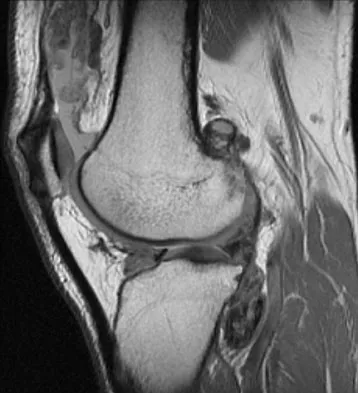

A 28-year-old man reports knee stiffness, swelling, and a constant ache that is worse with activity. Examination reveals an effusion, global tenderness, and warmth to the touch. Flexion is limited to 110 degrees. Figures 48a through 48d show sagittal T1-weighted, sagittal T2-weighted, axial T1-weighted fat-saturated gadolinium, and axial gradient echo MRI scans. Based on these findings, what is the most likely diagnosis?

Explanation